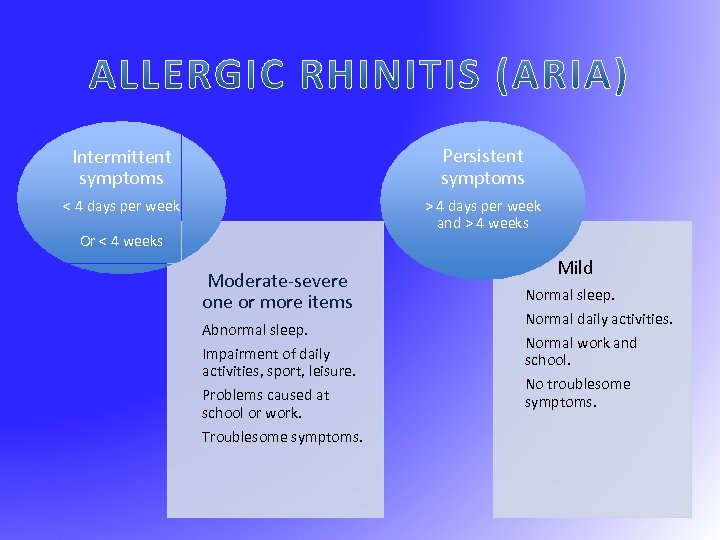

Intermittent symptoms Persistent symptoms < 4 days per week > 4 days per week and > 4 weeks Or < 4 weeks Moderate-severe one or more items Abnormal sleep. Impairment of daily activities, sport, leisure. Problems caused at school or work. Troublesome symptoms. Mild Normal sleep. Normal daily activities. Normal work and school. No troublesome symptoms.

Intermittent symptoms Persistent symptoms < 4 days per week > 4 days per week and > 4 weeks Or < 4 weeks Moderate-severe one or more items Abnormal sleep. Impairment of daily activities, sport, leisure. Problems caused at school or work. Troublesome symptoms. Mild Normal sleep. Normal daily activities. Normal work and school. No troublesome symptoms.